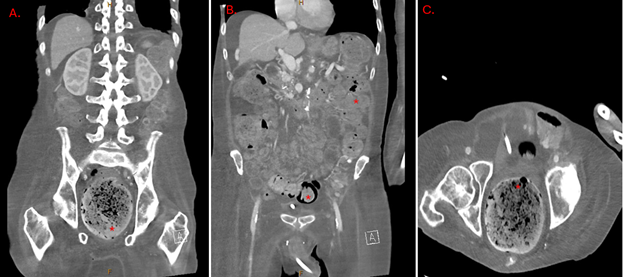

Case Presentation: Stercoral colitis (SC) is an uncommon yet life-threatening inflammatory condition caused by fecal impaction in the colon, leading to increased intraluminal pressure, ischemia, and inflammation. If untreated, complications such as necrosis, perforation, and sepsis can result in mortality rates as high as 63%. Clostridium species, particularly C. perfringens and C. ramosum, are rare causes of bacteremia but are associated with significant mortality. This report details a unique case of dual bacteremia with C. perfringens and C. ramosum in a patient with SC. A 60-year-old male with chronic obstructive pulmonary disease, type 2 diabetes, hypertension, and cachexia presented from his nursing home with hypotension, altered mental status, and shortness of breath. On arrival, his oxygen saturation was below 88% on room air despite baseline use of 1-2 liters of nasal oxygen. Examination revealed a cachectic, lethargic patient with generalized abdominal tenderness, distension, diminished bowel sounds, and confusion. Vital signs included blood pressure of 70/60 mmHg, respiratory rate of 27 breaths per minute, and a temperature of 36.7°C. Laboratory findings showed a white blood cell count of 5200/µL with 14% bandemia, platelets at 114×10³/µL, and an elevated lactate of 4.35 mmol/L. Imaging revealed a right lower lung infiltrate, fecal impaction, and findings consistent with stercoral colitis on CT. Initial treatment included antibiotics, bowel disimpaction, and supportive care. Blood cultures later identified C. perfringens and C. ramosum, prompting escalation to high-dose penicillin G and clindamycin. Despite aggressive resuscitation, the patient developed refractory hypotension and passed away on the third hospital day.